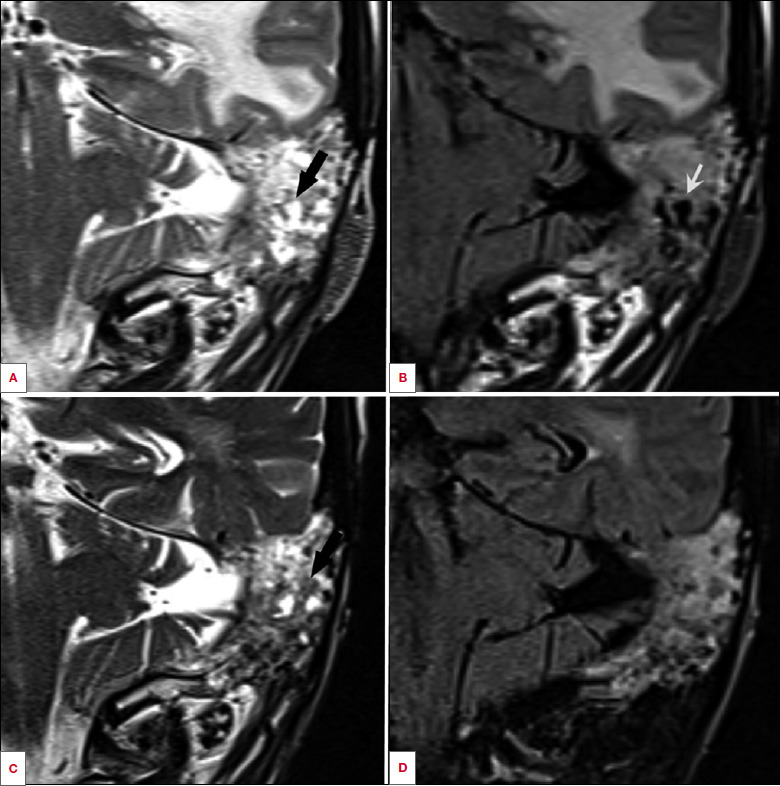

A case of otoliquorrhoea secondary to immunotherapy response in head and neck cutaneous squamous cell carcinoma. When abrupt response may worry the physician.

头颈部皮肤鳞状细胞癌免疫治疗反应继发耳咽炎一例。突然的反应可能会让医生担心。